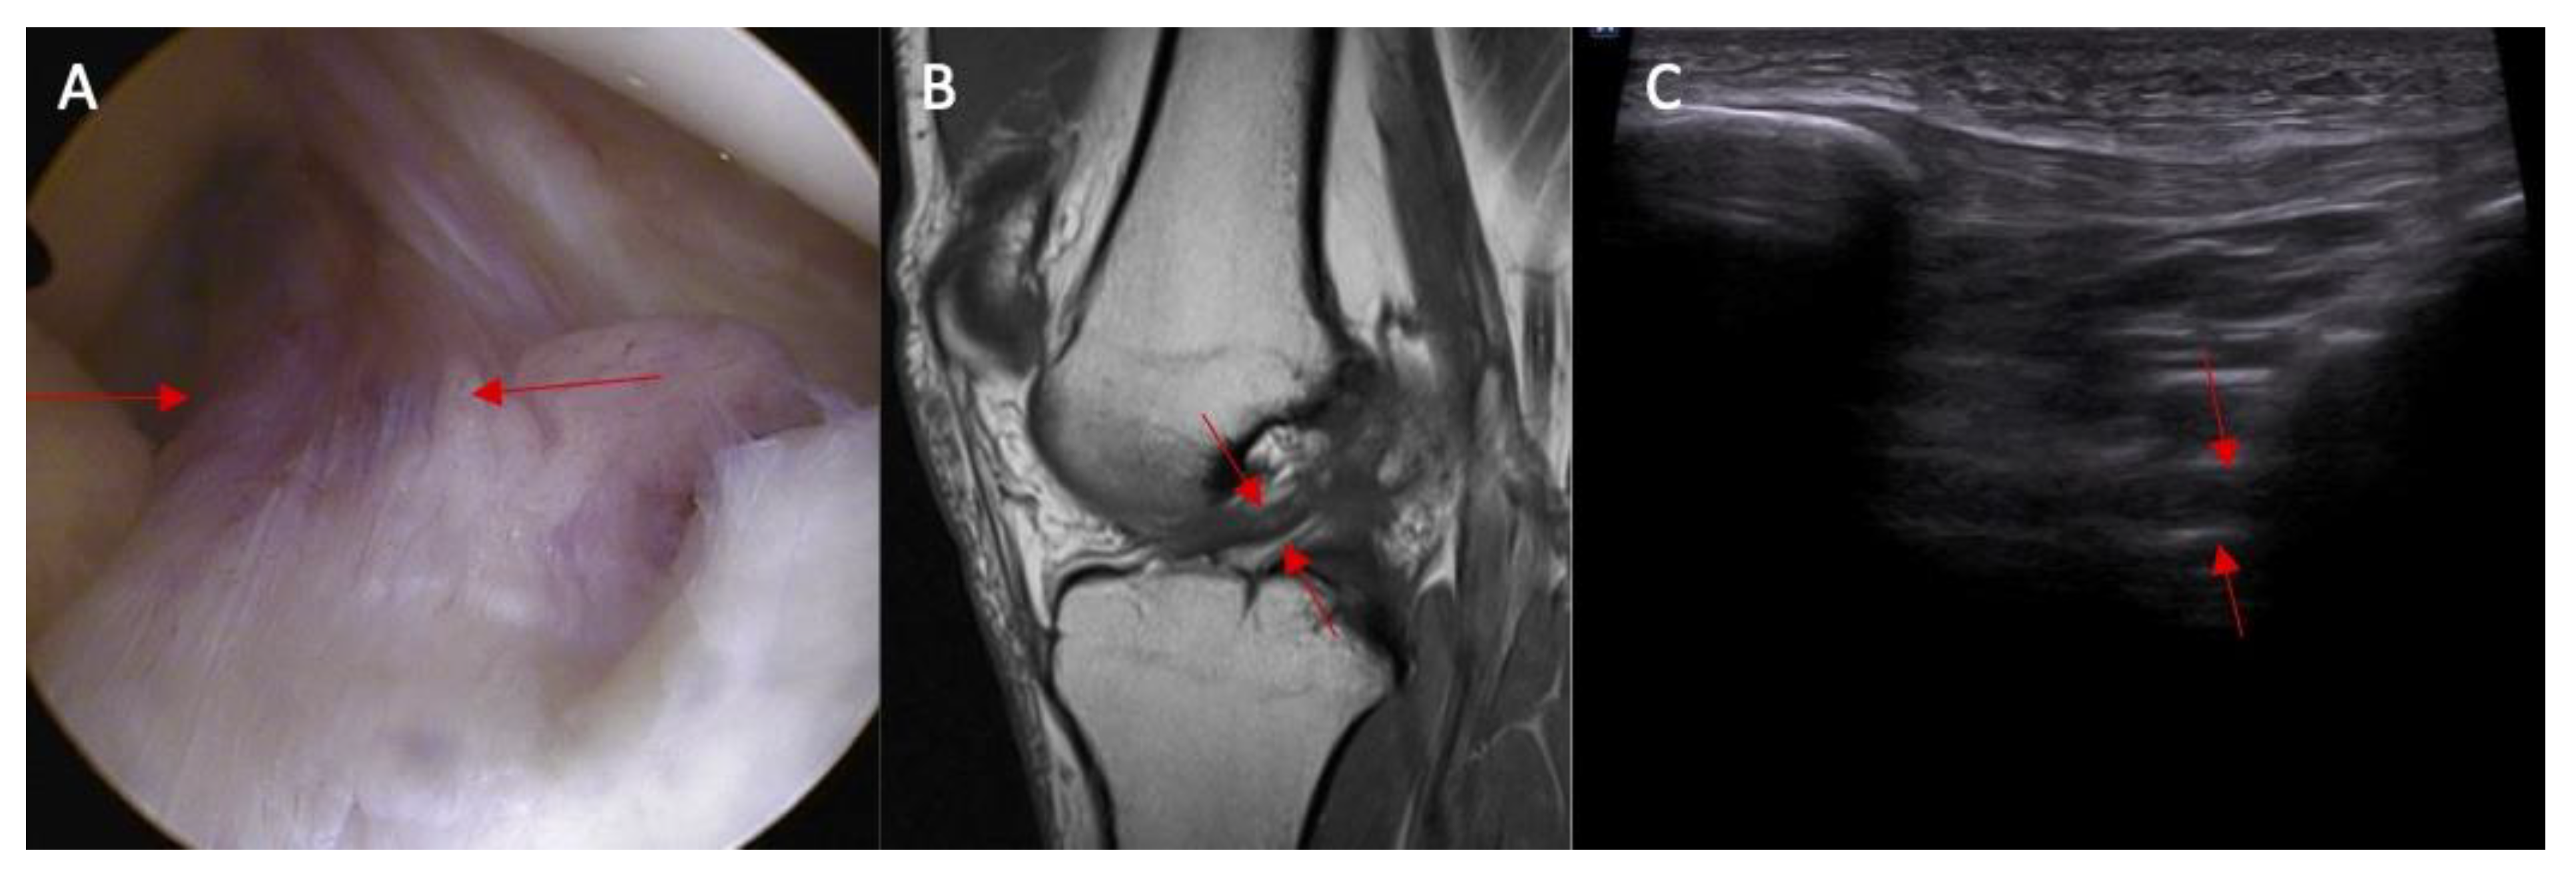

Abnormal inclination of the ACL in ultrasound was noted in 8% of patients without an ACL injury and in 67% of patients with an ACL injury (Figure 3 and Figure 4). Abnormal inclination of the ACL in ultrasound is more common in patients with an ACL injury (p < 0.0001). The odds ratio (OR) was 24 (95% CI and 4.50—127.96).

Figure 3.

The inclination of the ACL—the ultrasound view (ACL is marked with red arrows). (A) normal = 45 degrees angle between extension of posterior border of the ACL and base line and (B) abnormal < 40 degrees angle between extension of posterior border of the ACL and base line.

Figure 4.

(A) ACL tear confirmed in arthroscopy view and MRI examination; (B) (marked with red arrows); and (C) abnormal inclination of the ACL in ultrasound view.